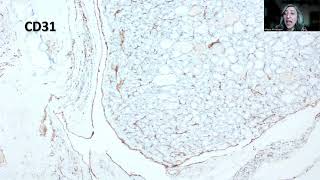

Vascular Invasion

Capsular And Vascular Invasion In Thryoid- Where...